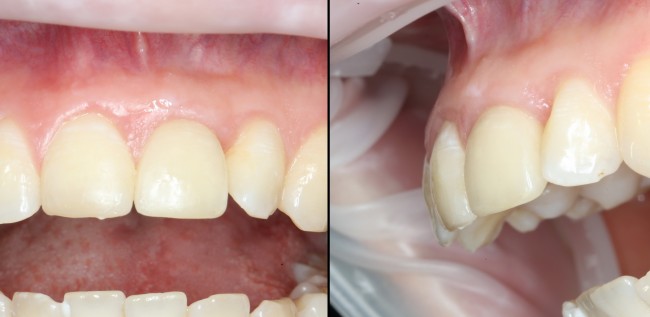

Через несколько месяцев после формирования десны, ортопед изготовил постоянную коронку:

И, на мой взгляд, получилось это очень неплохо. Сравните с тем, что было «до-«:

Наша пациентка это знает, поэтому через год заглянула к нам в клинику. И вот, что мы увидели:

На мой взгляд, это — уже хоть какой-то результат лечения. И, по мнению пациентки, с поставленной задачей мы справились.